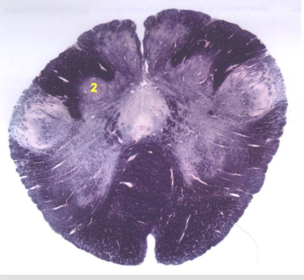

| Nucleus gracilis | |

| Nucleus cuneatus | |

| Fasciculus gracilis | |

| Fasciculus cuneatus | |

| Internal acruate fibers | |

| Lateral (external/accessory) cuneate nucleus | |

| Medullary pyramids | |

| Hypoglossal nucleus | |

| Hypoglossal nerve | |

| Dorsal motor nucleus of X | |

| Nucleus ambiguus | |

| Solitary tract | |

| Solitary nucleus | |

| ALS | |

| Medial lemniscus | |

| Medial longitudinal fasciculus | |

| Spinal tract of V | |

| Spinal nucleus of V | |

| Lateral (external, accessory) cuneate nucleus | |